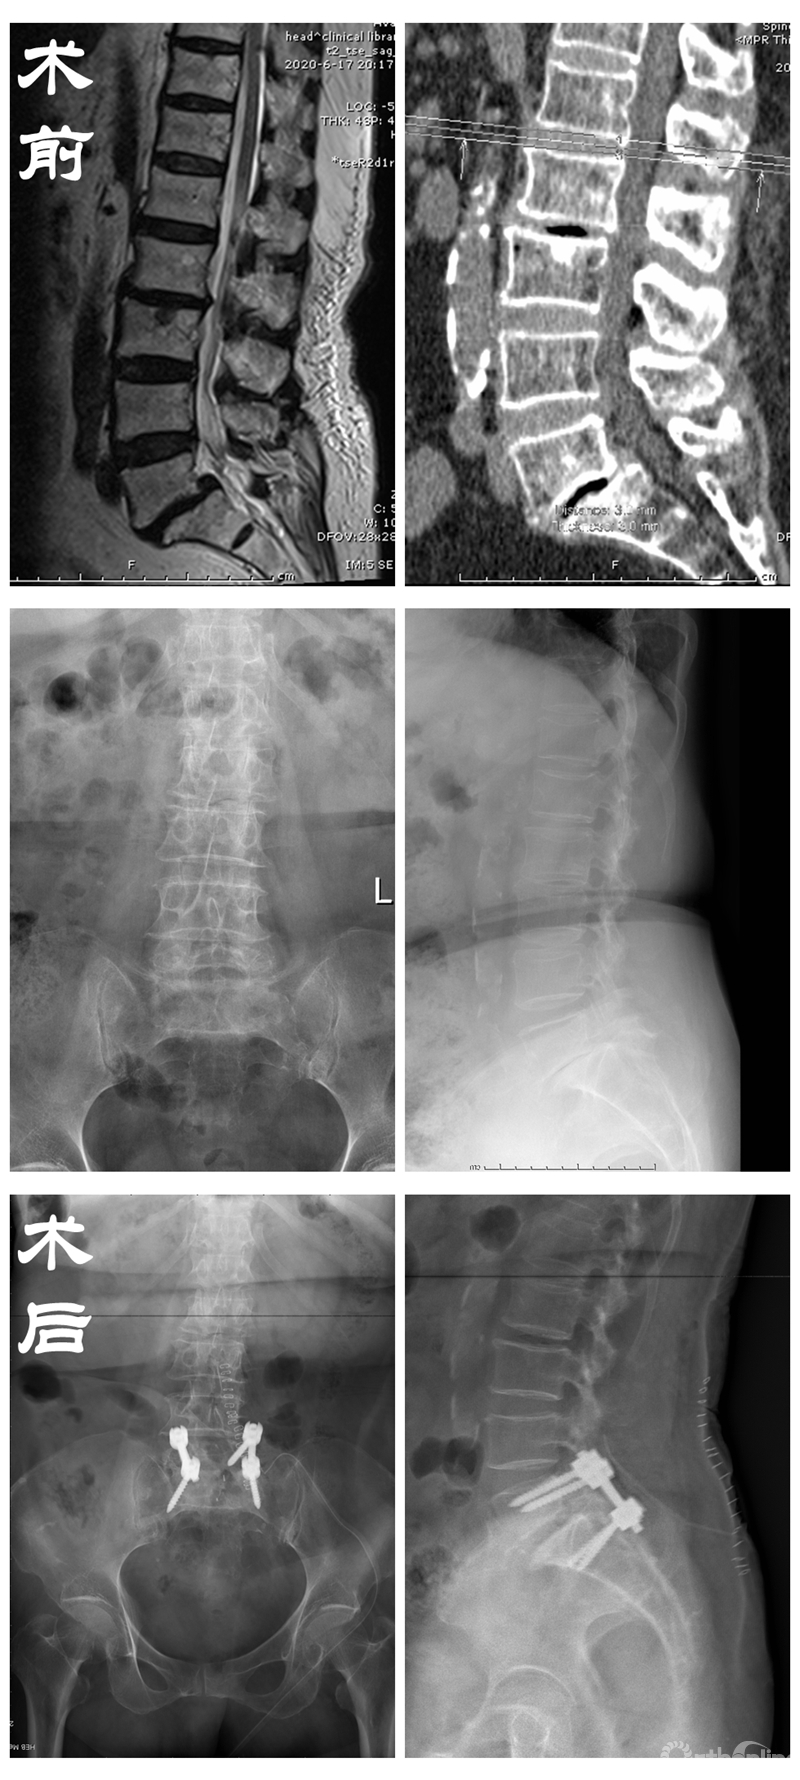

在备受折磨的患者苦苦央求下,丁文元教授为解决患者病痛,立即召集多科室进行会诊,在确认患者的心、肺、脑功能可以负担手术及麻醉后,为患者进行了腰椎切开复位固定融合术,术后患者腰腿疼缓解,日常活动均可自理。

患者资料